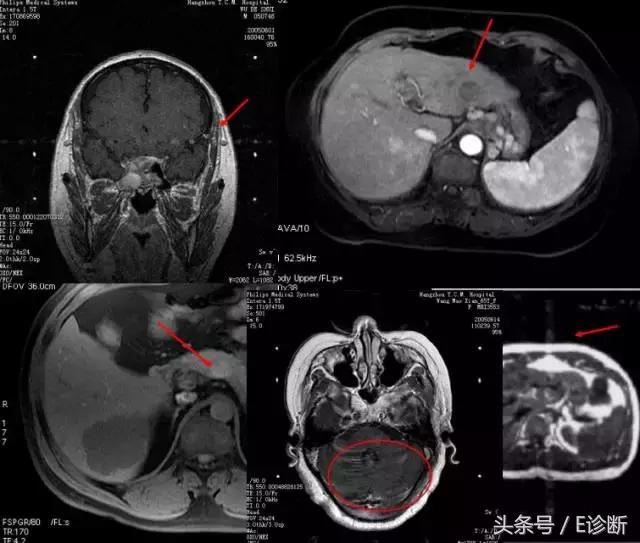

化学位移伪影

原因:

-

不同分子中氢质子以稍有不同的频率进动。在梯度场内,这些氢质子的位置将会被错误记录。

水内的质子相对向更高频率编码方向运动,而脂肪则相反。

位移导致在较低频率发生重叠,而较高频率处信号衰减。

水的进动稍快于脂肪中的质子进动。差异:3.5ppm

伪影特点:

出现在频率编码方向上(常规FSE序列或梯度回波)。在较低频率的方向出现一条亮带,而较高频率的方向出现一条暗带。

解决办法:

升高带宽

降低空间分辨率(Nx)

脂肪抑制

长TE